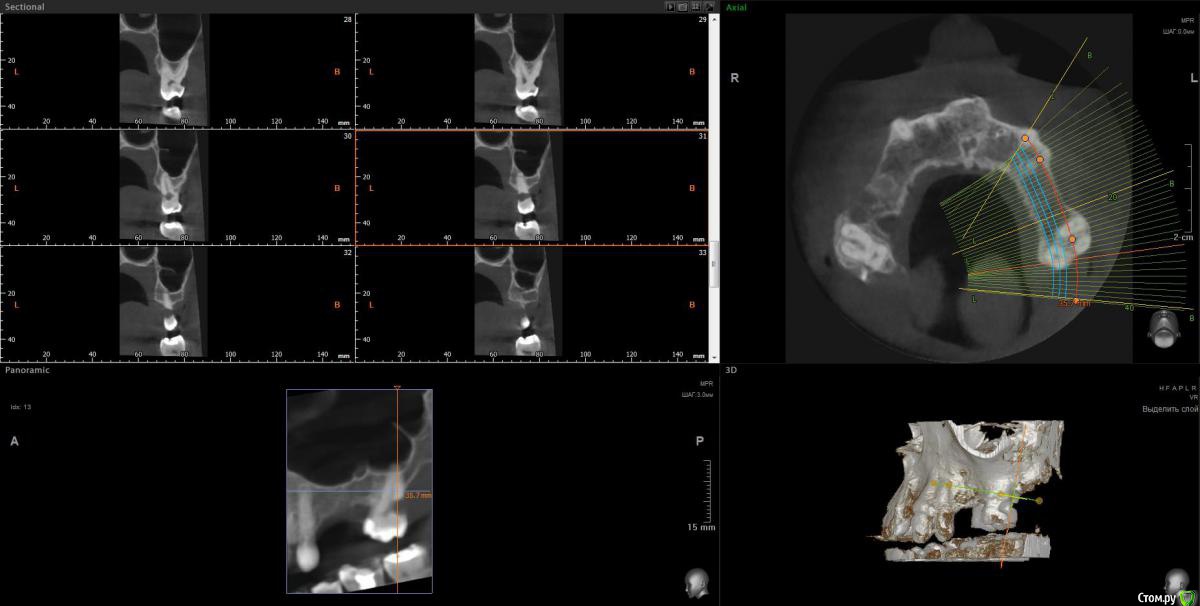

Просьба ко всем не равнодушным! Глянуть КТ верхней челюсти, 27 зуб  и место где удалили 16, может ещё где-то могут быть проблемы.  На фото видно где покраснение на дёснах, в этих местах возникают боли при движении головой. Бывает боль слева если засыпаю на левой стороне. Набуханий или флюсов нигде не видно.Прошу делиться мнениями, для меня это очень - очень важно. Стоматолог визуальных проблем на месте удалённого зуба не видит, всё зажило.

Зуб 27 требует внимания, необходим очный осмотр.

Также стоит обратить внимание на зубы 21 и 24